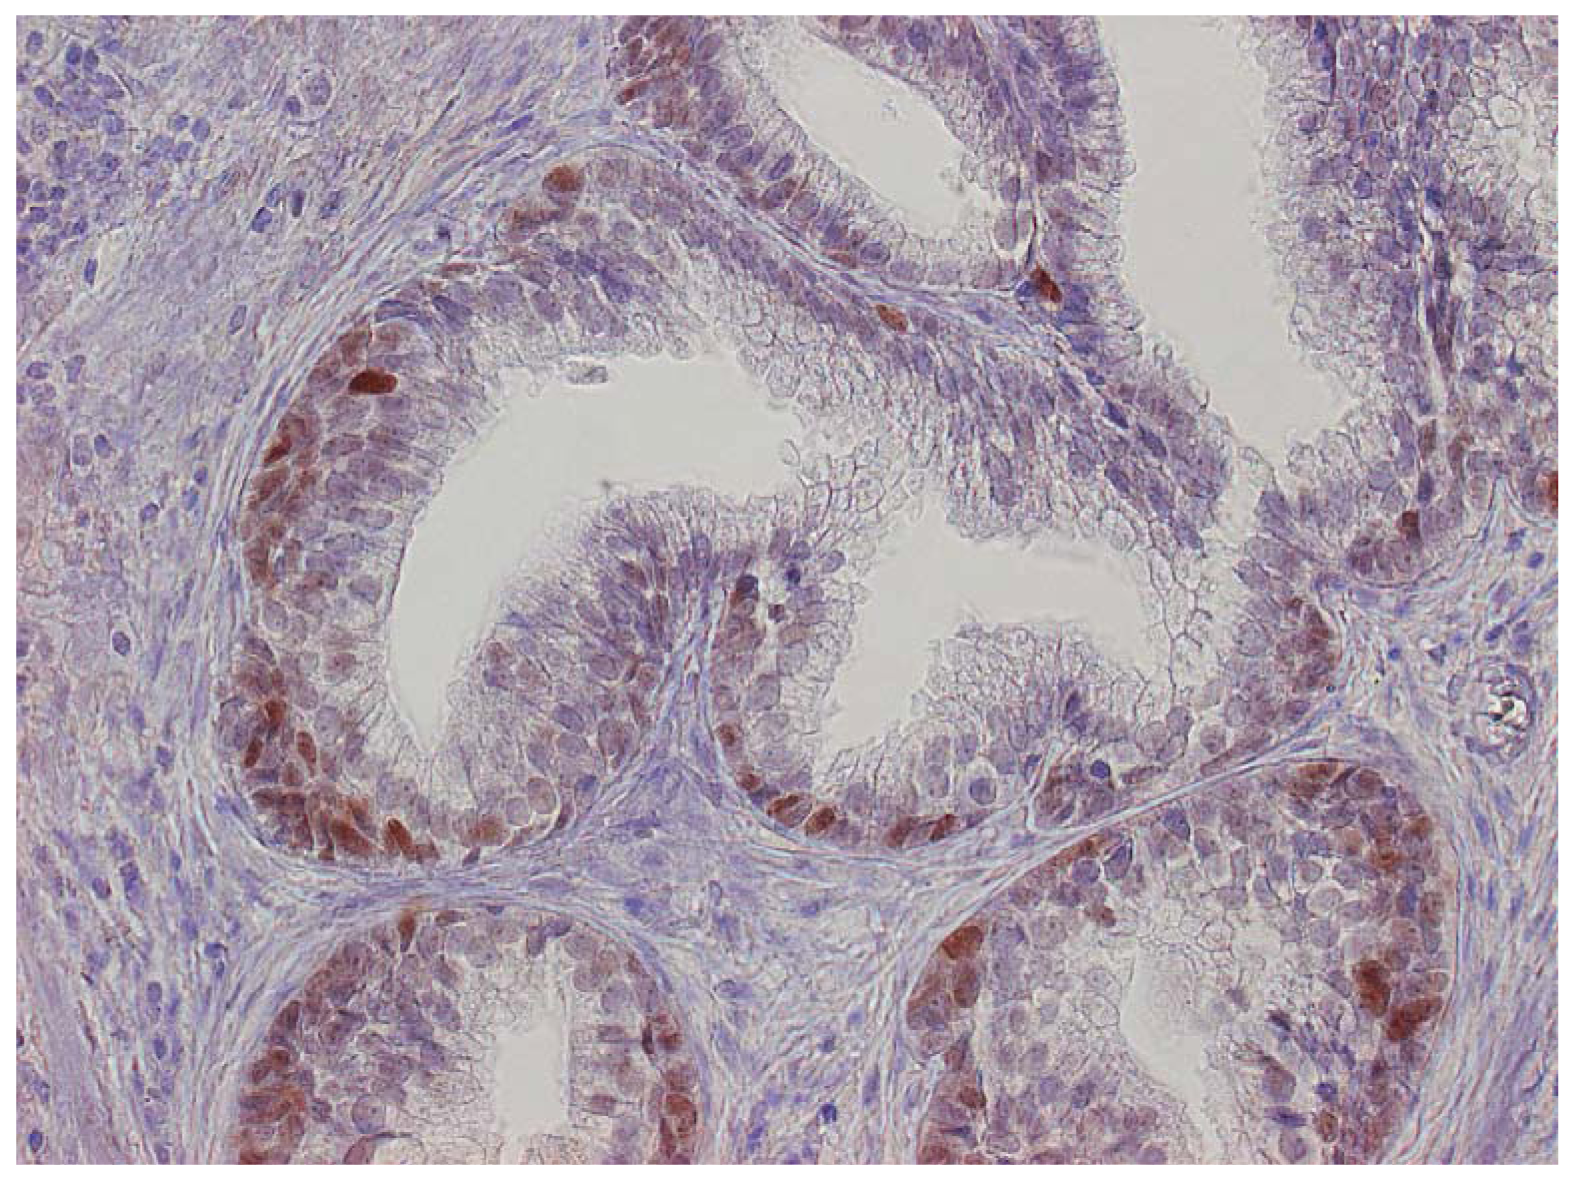

The major finding in the case-control study was no association of inflammation to prostate cancer risk, with no significant difference between cases and controls regarding inflammatory extent, and 48.3% of the cases were classified as severe inflammation and the corresponding number for controls was 49.7% (p = 0.83). There were no samples completely devoid of inflammation. Figure 1 shows examples of severe and mild-moderate inflammation. Figure 2 shows a loss of AR expression.

Expression of p53 was exclusively limited to the basal cell layer (Figure 3). The age of the paraffin blocks examined did not affect AR or p53 staining (data not shown).

To classify inflammation in the BPH specimens, we used a dichotomous scale. The definition of inflammation was mild-moderate or severe inflammation. Definition of severe inflammation was infiltration of inflammatory cells covering one-third or more of the specimens with either diffuse or multifocal pattern of inflammatory cells. Inflammatory cells should be present in confluent sheets in at least three large different tissue chips or covering one-third of the slide. Patterns of inflammatory tissue destruction, defined as a disruption of the epithelium, fell into the severe category. The mild to moderate inflammation was defined as areas of confluent sheets of cells or very small ones, no tissue destruction, and less than a third of the area covered. Our definition of severe corresponds to the consensus classification by Nickel et al. [18] of moderate and severe grade together with multifocal and diffuse extent. Our classification of mild to moderate relates to all other patterns defined by Nickel.

In this group of cases, a small pilot study of ten cases with controls were randomly selected and evaluated for different inflammatory cell markers—CD3, CD 20, and CD68, corresponding to T-cells, B-cells, and macrophages—and for AR and p53. Cases and controls were compared regarding patterns and distribution of the different cells. For each of the inflammatory cell types, we evaluated distribution, extent, and grade according to the proposed consensus by Nickel et al. [18]. After the pilot study, we randomly selected 50 cases and their corresponding controls. From this group five cases and two controls were missing in the archives, making it 45 cases and 48 controls. This was done to investigate whether differences in immunohistochemistry patterns of the Androgen Receptor (AR) or p53 could be a risk factor for developing prostate cancer. Normally, both luminal epithelial and stromal cells express AR in the nucleus. To evaluate loss or weakened expression of AR, we counted 30–40 luminal epithelial cells in 10–15 visual fields throughout the specimen at 400× magnification. Definition of loss was no staining in the nucleus; weakened expression was defined as less than half of the staining intensity compared to adjacent normal staining glands.